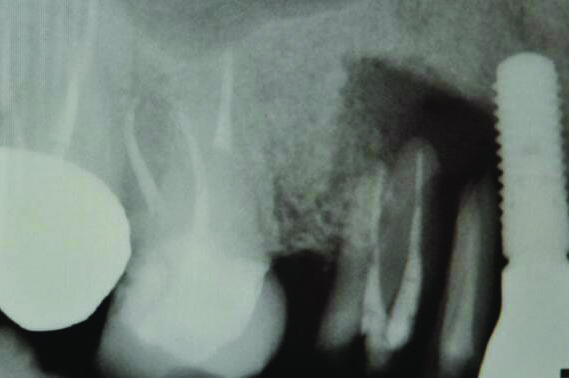

Fig 3 and Fig 4. Case 2: Initial clinical presentation showing implant No. 6 with RPI, having been impacted by fractured tooth No. 5 (Fig 3); radiograph showing fractured tooth No. 5 with periapical lesion extending to the distal aspect of implant No. 6 (Fig 4).

Fig 4. Case 2: Initial clinical presentation showing implant No. 6 with RPI, having been impacted by fractured tooth No. 5 (Fig 3); radiograph showing fractured tooth No. 5 with periapical lesion extending to the distal aspect of implant No. 6 (Fig 4).

Patient 2: A 63-year-old healthy male patient presented with implant No. 6 exhibiting RPI, having been affected by previously endodontically treated and fractured tooth No. 5 (Figure 3 and Figure 4). The implant had probing depths ranging from 4 mm to 10 mm (Table 1) with the most severe bone loss at the distal aspect of implant No. 6 (Figure 3 and Figure 4).